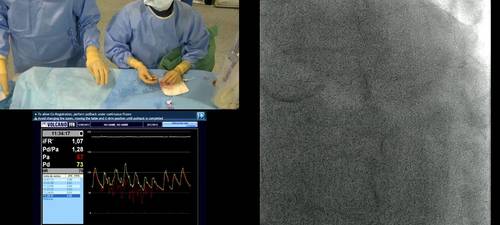

Prof Javier Escaned hosts a live case transmission from Clinico San Carlos, Madrid, Spain.

Live case transmission from Madrid